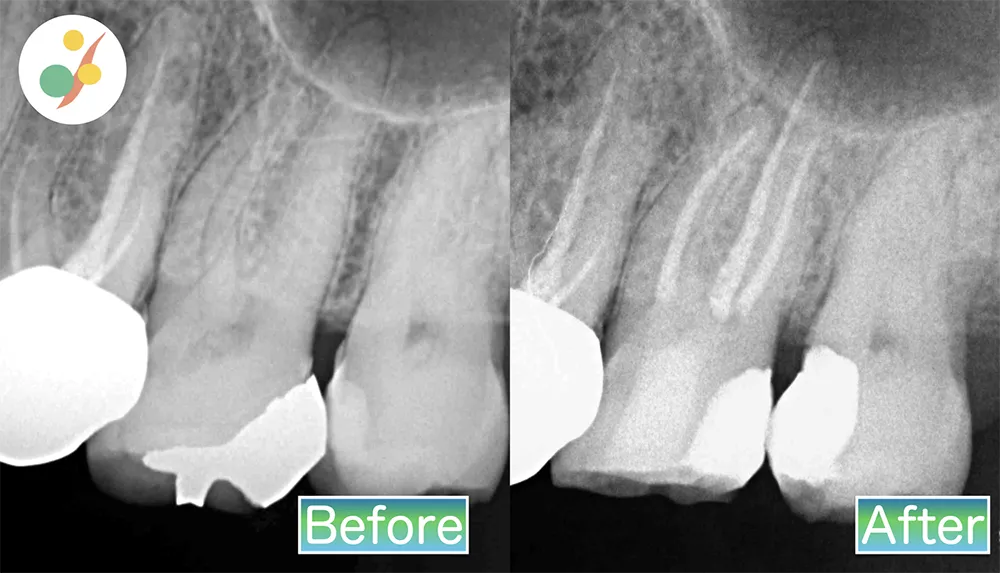

根管治療

治療の内容:マイクロスコープを使用した精密根管治療(抜髄)

治療費用:¥88,000(税込み)

リスク:術後に痛みや腫れが出ることがあります。

治療期間:1回

当院の根管治療は、できるだけ歯を温存できるように拡大率が20倍のマイクロスコープを使って、歯根にある神経を丁寧に治療します。